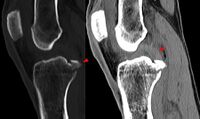

hinterer Kreuzbandriss (Röntgen)